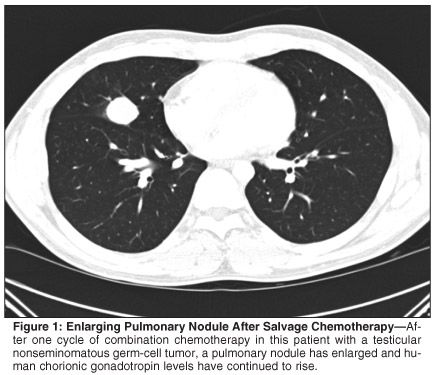

A healthy 25-year-old male was diagnosed with right testicular nonseminomatous germ-cell tumor with small-volume retroperitoneal metastases. Retroperitoneal lymph node dissection (RPLND) revealed 2 out of 13 positive nodes. Post-RPLND, the patient was followed with close surveillance. Three months later, human chorionic gonadotropin (HCG) levels rose precipitously and two pulmonary nodules were seen on chest imaging. Three cycles of bleomycin, etoposide, and cisplatin were administered, resulting in normalization of serum markers and radiographic abnormalities. Within 3 months of chemotherapy, HCG again rose to 1,006 ng/mL and a new pulmonary nodule was observed. Brain magnetic resonance imaging and testicular ultrasound ruled out disease recurrence in sanctuary sites. Salvage chemotherapy with vinblastine, ifosfamide, and cisplatin was initiated. After one cycle, the pulmonary nodule had enlarged (see Figure 1) and HCG continued to rise.

The patient underwent resection of the growing pulmonary nodule. Pathology revealed choriocarcinoma; serum markers normalized postoperatively (see Figure 2). The patient is alive without evidence of disease at 5 months postresection.